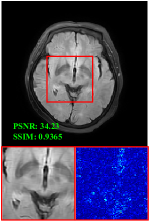

Figure 5 provides the qualitative comparison of the various methods on the four datasets at a scale of 4. The top, second, third, and bottom rows are the SR results under the FastMRI, clinical brain, clinical tumor and clinical pelvic datasets, respectively. The red boxes indicate the zoom-in region of complicated anatomical structures along with their corresponding error maps. Note that the brighter textures in the error maps, the lower the quality of the reconstructed images. As can be seen, compared to methods based on Transformers and CNNs, diffusion-based methods like DisC-Diff and DiffMSR (Ours) are capable of reconstructing high-realistic images with promising reconstruction metric scores (PSNR and SSIM). Nevertheless, while DisC-Diff can reconstruct high-precision MR images, it does not preserve the structure present in the original HR images, introducing some additional information that can affect medical diagnosis. In contrast, our method combines DM and PLWformer, which can preserve the original image’s structure while restoring high-frequency information.

Effect of Condition. To evaluate the effect of the condition extraction module, we design a variant by removing CE (named as w/o CE), which means that condition is not employed in the denoising process, as shown in Table 2. As can be seen, without condition , the reconstruction performance decreases, which demonstrates that condition extracted by the CE can provide supplementary information for the denoising network. Besides, Figure 6 provides a qualitative comparison w/o CE. As can be seen, without condition , the reconstructed image will lose some complicated anatomical structures.

In this section, we present more visual qualitative comparisons. Figures 8, 9, 10, and 11 show the reconstruction results of each method in FastMRI, clinical brain, clinical tumor, and clinical pelvic, respectively. As can be seen, although DisC-Diff can reconstruct MR images with high-frequency information, it fails to preserve the structure and content of the original Target HR image effectively, resulting in image distortion. In contrast, our proposed DiffMSR can restore high-frequency information while preserving the structure of the original HR image, indicating the effectiveness of the joint use of DM and PLWformer.